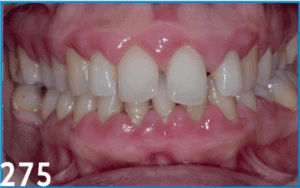

La prise en charge orthodontique des encombrements antérieurs chez l’adulte ne peut être dissociée d’une évaluation parodontale rigoureuse. Ce cas clinique illustre la nécessité d’une collaboration étroite entre orthodontiste et parodontiste afin de respecter les limites biologiques et de garantir la stabilité à long terme. Après un diagnostic complet incluant une classification parodontale selon les critères de l’EFP 2017, une stratégie thérapeutique conjointe a été établie : assainissement initial, apport gingival préalable, puis mouvements orthodontiques planifiés par setup numérique. Cette démarche intégrée a permis de restaurer l’esthétique et la fonction, tout en préservant le support parodontal. Le succès repose sur un suivi pluridisciplinaire et une communication constante entre les différents acteurs de soins.